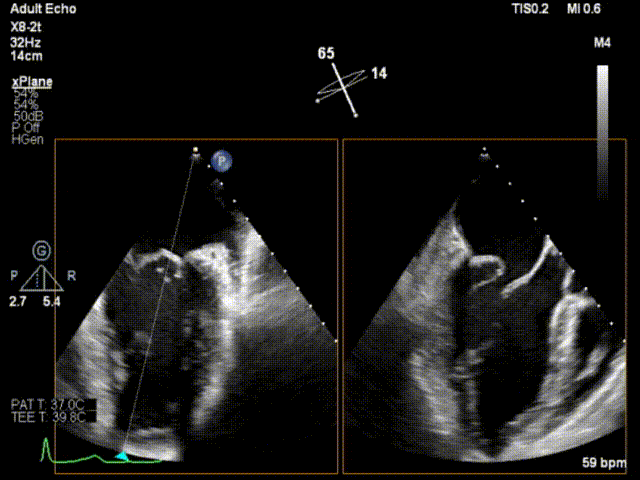

患者男性,63岁,主诉间歇性心悸5年,加重3月。门诊以“二尖瓣关闭不全”收入西京医院。术前超声提示:二尖瓣关闭不全,前叶26mm,后叶22mm,二尖瓣腱索断裂,后叶P1区及部分P2区脱垂,脱垂高度9mm,脱垂宽度15mm,舒张期瓣口面积约6.8cm²,反流束位置位于1区偏2区,Carpentier分型Ⅱ型,心功能Ⅳ级(NYHA分级)。

术前超声心动图2